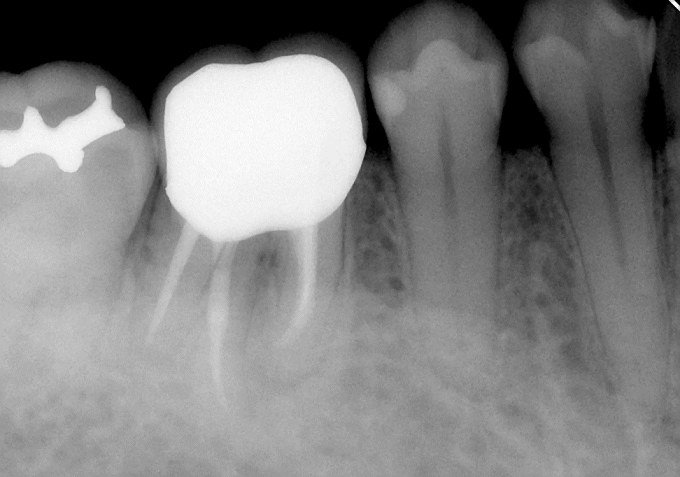

こんな感じに無事終了することが出来ました。結構曲がりくねった神経の通り道ですね~。

その後は、土台と仮歯を入れて経過観察させていただきました。

その後は、症状も特になく経過良好であることからかぶせ物を入れて終了となりました(^0^)/

終了時はこんな感じ!